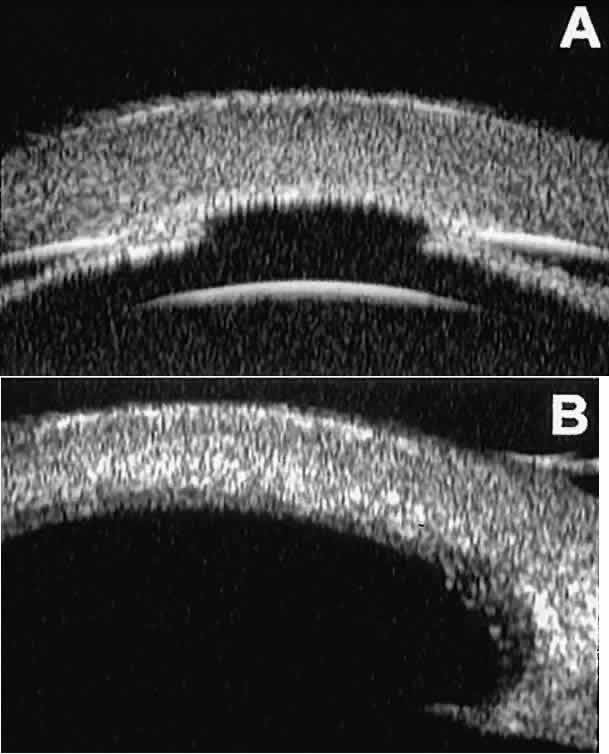

The role of UBM in the preoperative assessment of eyes with cataract is as yet unknown. In certain eyes, however, UBM may reveal features or abnormalities that could alter the ophthalmologist's surgical approach. Postoperatively, UBM can show the size and location of an intraocular lens (IOL) and the positioning of the haptics. A posterior chamber IOL appears on UBM as a highly reflective plate (corresponding to the lens optic) in the retropupillary plane with reverberation artifacts behind it (Fig. 17A). In contrast, an anterior chamber IOL appears on UBM as a sonoreflective plate located anterior to the pupillary plane (see Fig. 17B). In most eyes with a posterior chamber IOL, UBM can show whether the haptics are in the capsular bag (Fig. 18A), in the ciliary sulcus (see Fig. 18B), or in some other anatomic location12 (e.g., resting on the peripheral iris or secured with sutures to the sclera). The haptics are easier to locate if they are made of polymethyl-methacrylate than if they are made of proline because the former has a stronger reflectance.

Fig. 18 . Localization of posterior chamber IOL haptics by UBM. A. Haptic in capsular bag (arrow). B. Haptic (bright object just behind peripheral iris) in iridociliary sulcus.